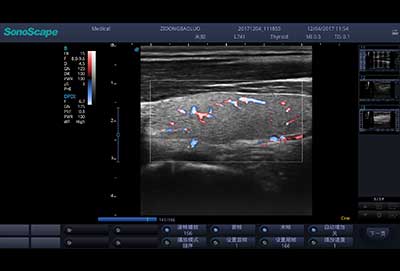

E3便携式彩色多普勒超声诊断系统拥有专业超声技术平台、高度集成化的硬件模块和结构设计、简便的操作流程、支持三探头接口全激活,兼顾了优质图像、轻便机身以及台便两用的临床使用需求。无论在常规超声科门诊检查,还是在急诊、麻醉、ICU、户外等各种应用场景。都能给您带来流程的操作体验。

血管内中膜自动测量